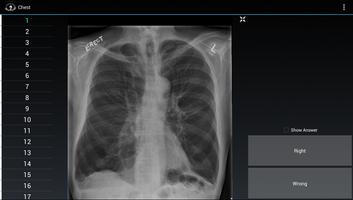

Radiology Flashcards: Free包含來自放射性水面卡系列醫學教育應用程序的25個示例圖像和教學點,每個人,胸部,Neuro,Mammo和MSK應用程序中有5個樣本。

放射學抽認卡專為放射學居民和同胞教育而設計。醫師,居民,醫學生以及有興趣從事醫學成像職業的任何人也將發現這些應用程序有用。

每個版本都為用戶提供了100個高質量的交互式圖像,包括超聲,純電影,CT和MRI。在抽認卡的另一側是正確的診斷,然後是一個可以記住的簡短事實。